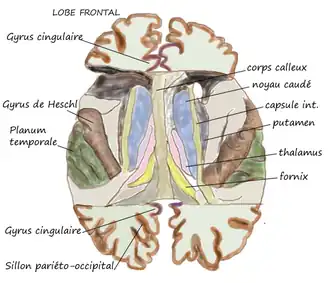

The planum temporale is the cortical area just posterior to the auditory cortex (Heschl's gyrus) within the Sylvian fissure.[1] It is a triangular region which forms the heart of Wernicke's area, one of the most important functional areas for language.[2] Original studies on this area found that the planum temporale was one of the most asymmetric regions in the brain, larger in the left cerebral hemisphere than the right.[3]

The planum temporale makes up the superior surface of the superior temporal gyrus to the parietal lobe.[4] The posterior extent of the planum temporale has been variably defined, which has led to disputes to estimates of size and degree of asymmetry.[4]